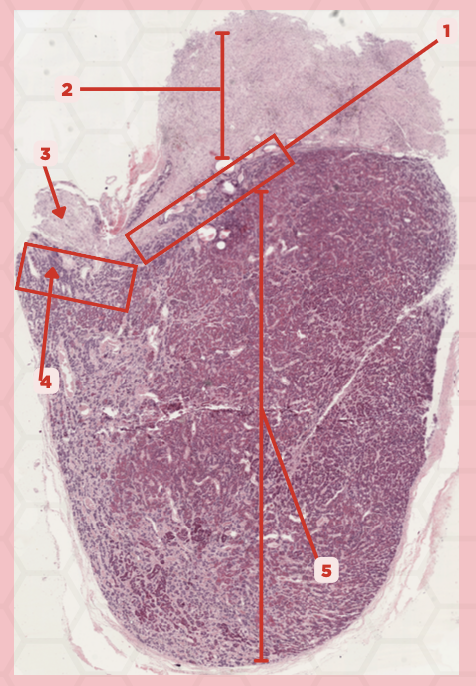

Pituitary

Identify the specimen.

Anterior Lobe

Identify the structure labeled as 1.

Posterior Lobe

Identify the structure labeled as 2.

Intermediate Lobe

Identify the structure labeled as 3.

Pars Tuberalis

Identify the structure labeled as 4.

Pituitary Stalk

Identify the structure labeled as 5.